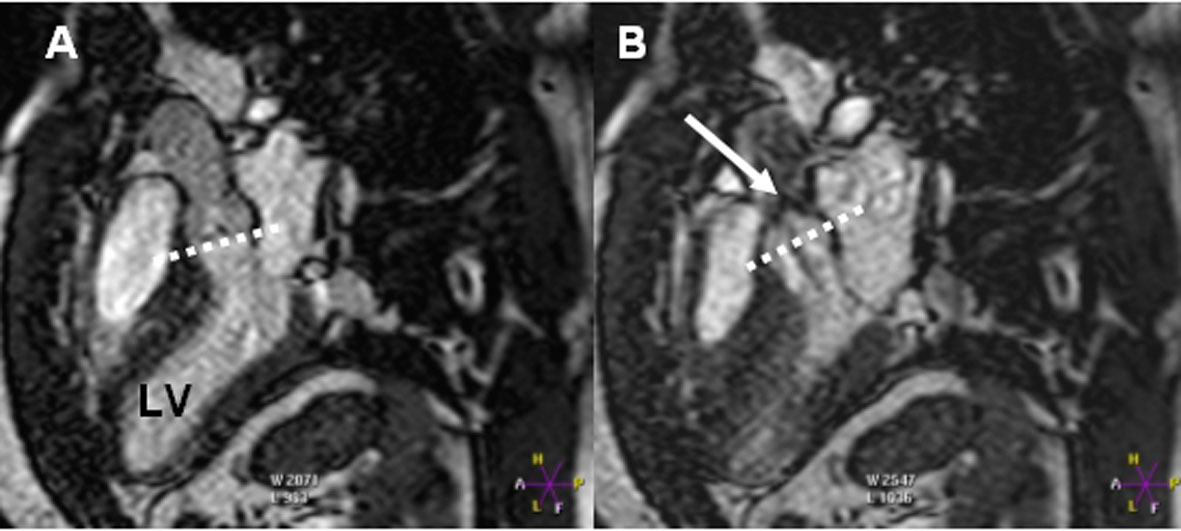

We present a case of a 28 years old male with delayed diagnosis of a severe supravalvular aortic stenosis accompanied with peripheral pulmonary artery stenosis and increased right ventricular pressure. The patient had been diagnosed since he was 3 years old to suffer from pulmonary artery hypertension of idiopathic origin. The diagnosis was made by tranthoracic echocardiography and magnetic resonance imaging.